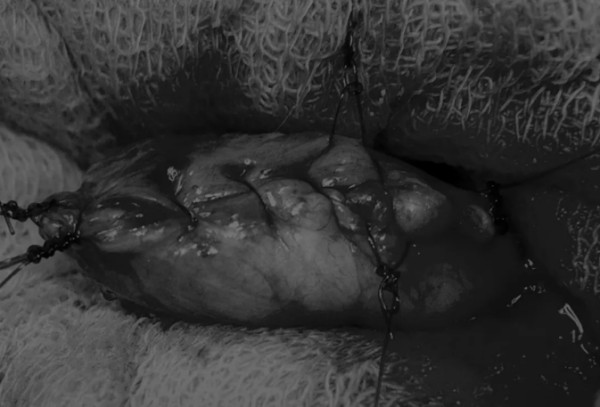

在中线开腹手术后,确定膀胱,将其取出并隔离(图1)。为了使膀胱持续暴露,可在膀胱中线两侧各放置一根固定缝线(图2)。

图1 将膀胱从腹腔中取出,用无菌外科敷料隔离。为了防止膀胱滑入腹部,可在膀胱顶部放置一根固定缝线,由助手通过止血钳夹住固定缝线做持续牵引